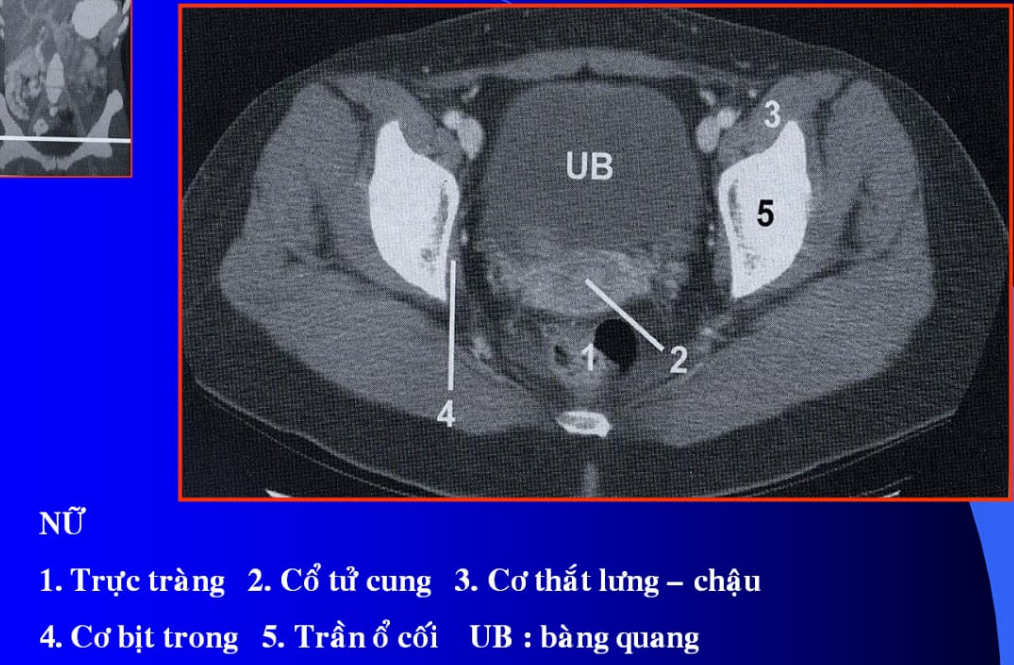

cq trong hình ?

cơ tl? cơ chậu?